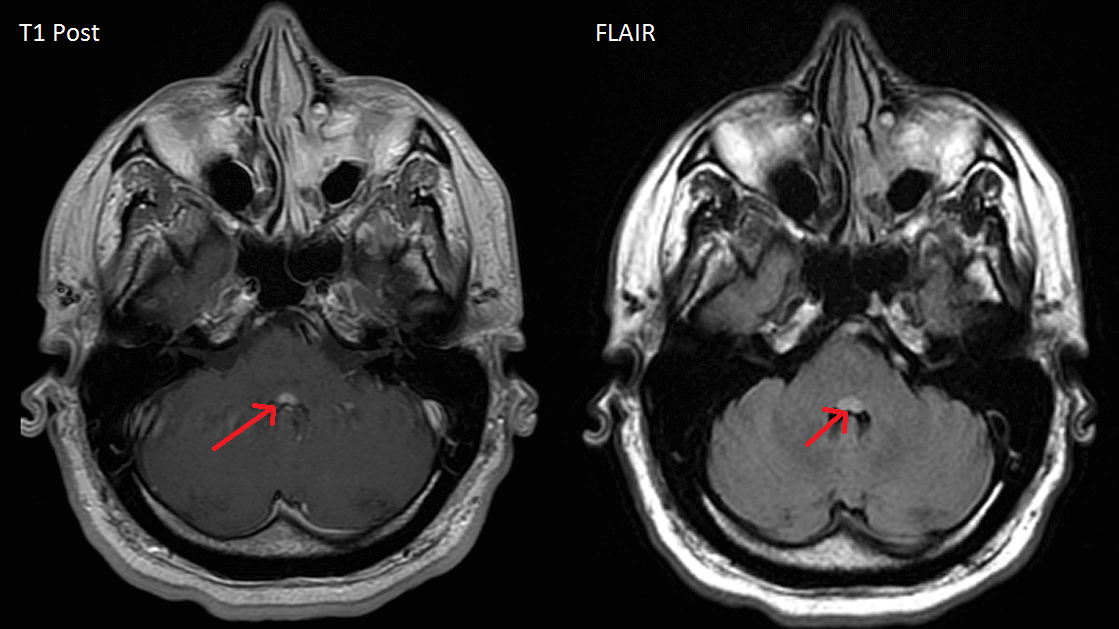

The facial colliculi sit on the dorsal aspect of the pons, forming part of the floor of the fourth ventricle. Both facial colliculi are highlighted in the image below.

Lesions that affect bilateral facial colliculi are rare, but in the case shown here both are affected by what is likely multiple sclerosis or other demyelinating disease (positive oligoclonal bands and other non-enhancing periventricular white matter lesions). The effects of a lesion are determined by the structures that constitute the facial colliculus, specifically the nucleus of the abducens nerve (CN VI), the facial nerve that wraps around the abducens nucleus, the paramedian pontine reticular formation (PPRF) that sits near the abducens nucleus, and the medial longitudinal fasciculus (MLF).